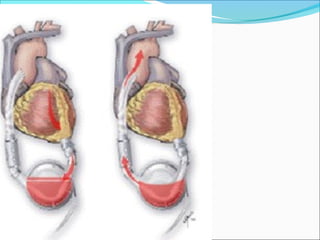

 (A) Balloon inflation during left ventricular (LV) diastole

occludes the descending thoracic aorta, closes the aortic valve,

and increases proximal coronary and cerebral perfusion. (B)

Balloon deflation during LV systole decreases LV afterload and

myocardial oxygen demand.